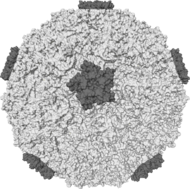

Rhinoviruses cause most common colds |

Common colds are most often caused by infection by one of the more than 100 serotypes of rhinovirus, a type of picornavirus. Other viruses causing colds are coronavirus, human parainfluenza viruses, human respiratory syncytial virus, adenoviruses, enteroviruses, or metapneumovirus. Due to the many different types of viruses, it is not possible to gain complete immunity to the common cold.